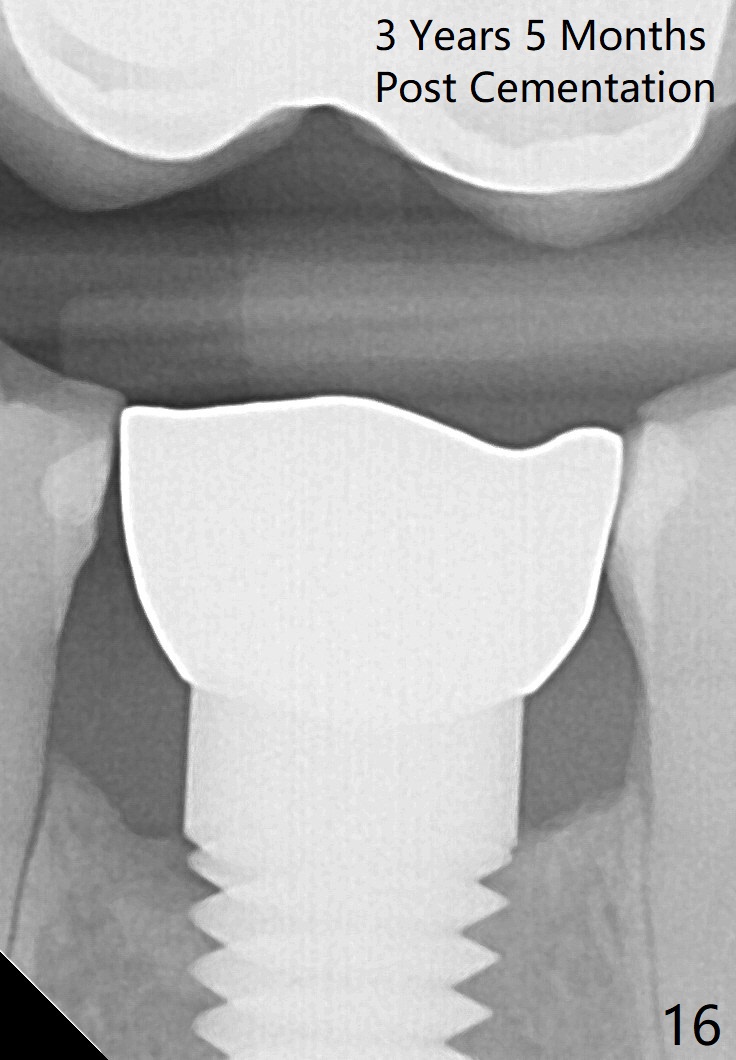

Eleven months post bonding (17 months postop), there is cortical bone formation at the mesial and distal crests (Fig.14).  It remains the same 1 year 10 months post bonding (Fig.15).  There is no bone loss 3 years 5 months post cementation (Fig.16).  In fact the crestal cortical bone thickens.